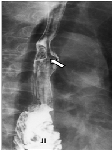

Sarcoidosis as Hepatic, Splenic, and Para-aortic Lymph Nodules, Mimicking Colon Cancer Metastases: A Case Report

Kenichi Maeda, Nobuhisa Matsuhashi*, Takao Takahashi, Tomonari Suetsugu, Yoshinori Iwata, Takeharu Imai, Toshiyuki Tanahashi, Satoshi Matsui, Hisashi Imai, Yoshihiro Tanaka, Kazuya Yamaguchi, Shinji Osada, Kazuhiro Yoshida